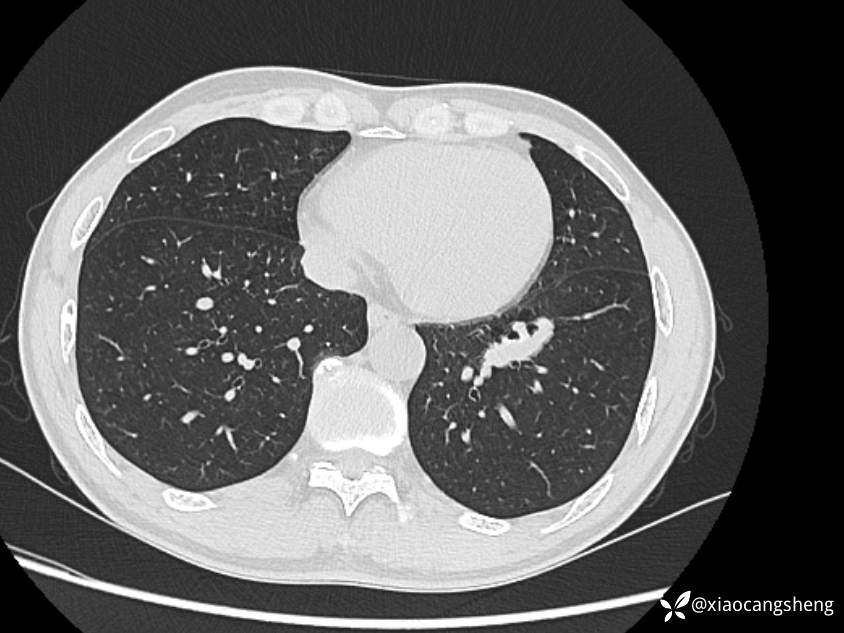

行胸部CT示肺气肿,支气管炎,左下肺局限性之阔,血管聚集及增粗。

2023-09-06胸部CT表现: